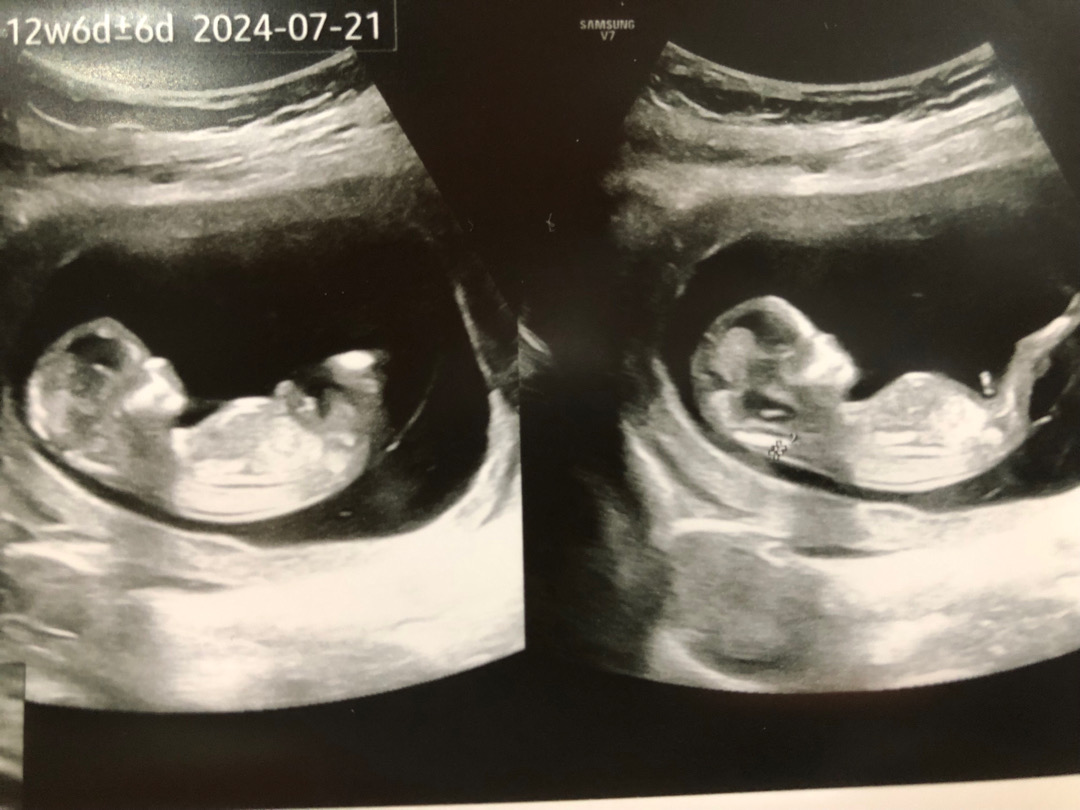

12주2일차 오늘 초음파 각도법 고수님들 봐주세용

원장님이 한달뒤에 알려주신다구 힌트도 안주셨어용~~ 저 다리 아래 있는게 탯줄인가요? 아님..🤔 생각하는게 맞다면 각도법으로 한번 봐주세용❤